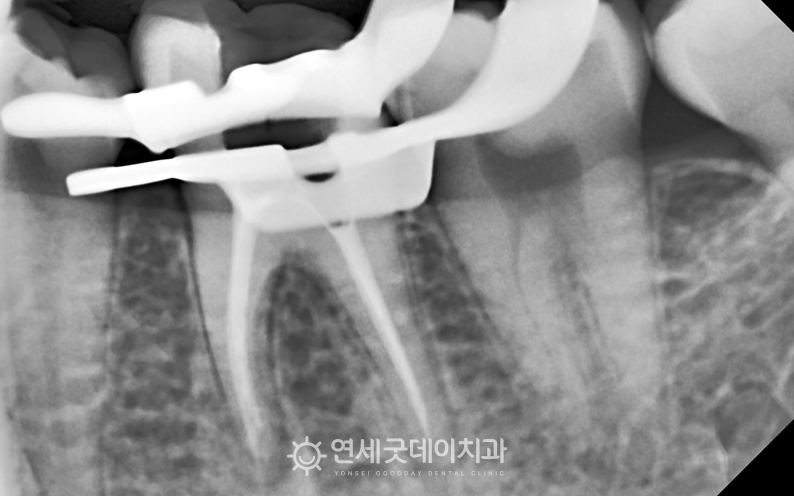

● 담당과 : 보존과 어금니 부위의 큰 충치를 주소로

#27, 36 부위에 큰 충치가 관찰되며

두 부위 모두 발치를 고려할 정도로 큰 충치였으나 또한 사진상 표시된 부위의 인접 치아는

신경치료를 통해 손상된 신경관을 제거 및 소독한 뒤 환자분은 치아 머리가 많이 손상된 상태였기 때문에

자연치아 살리기 과정 중 이후 약해진 치아를 보호하고

이어서 #27 부위도 신경치료를 진행하였으며